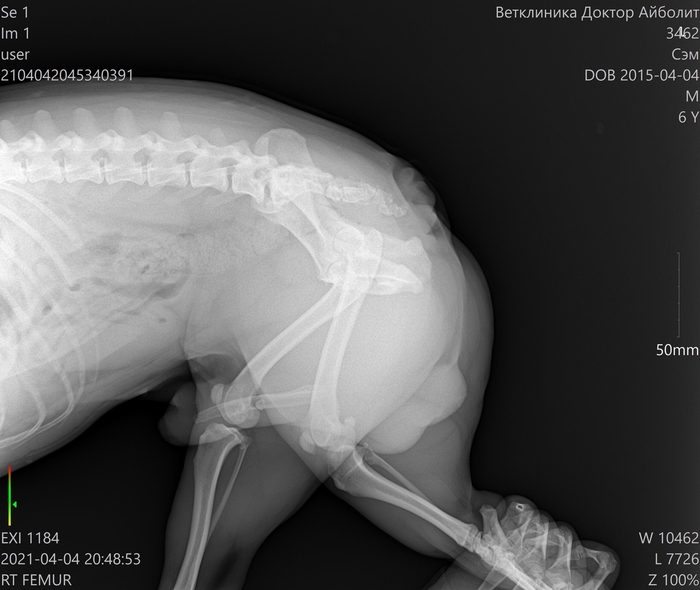

Друзья, у моей собаки, французский бульдог Сэм, вчера отказали задние лапки. Рентген показал дисплазию тазобедренного сустава, а из за этого произошло то что позвоночник немного смещался и поджал спинной мозг. Для доаперабельного лечения нужно 4 укола Метипреда, тоесть две баночки. Одну баночку я нашёл.

Ето мы после капельницы;)